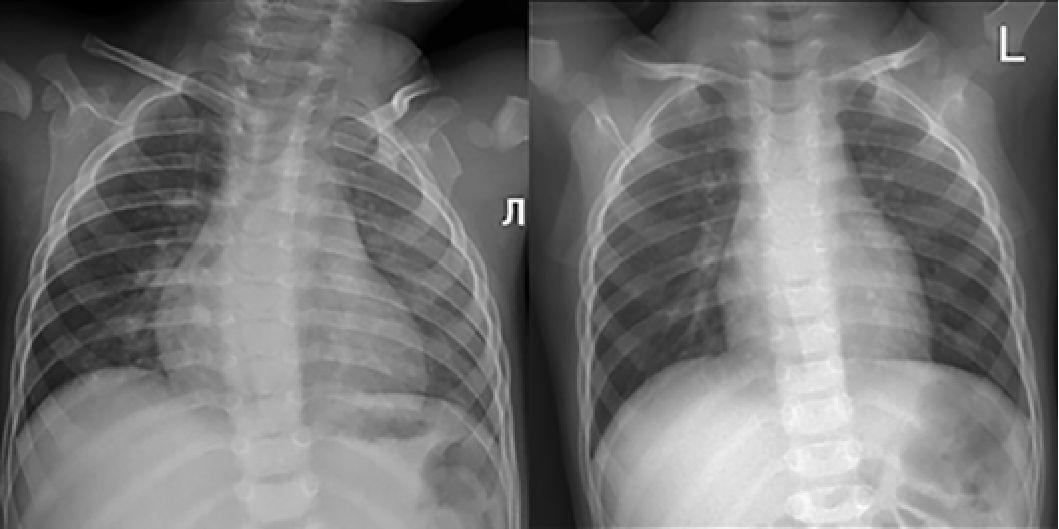

После инициации терапии уменьшились и достигли нормы показатели толщины миокарда (толщина задней стенки левого желудочка уменьшилась с 6,7 мм до 5 мм, межжелудочковой перегородки с 7,8 мм до 5,5 мм) (рис. 6, 7). По течению порока сердца также отмечена положительная динамика. Размеры дефекта при последнем обследовании уменьшились до 6 мм (рис. 8), ГСД между желудочками нарастает и нормализовался КДР ЛЖ (рис. 9, 10). Улучшение отмечено и по результатам рентгенографии ОГК с разницей в 1 год (рис. 11).

Рис. 11. Рентгенограмма органов грудной клетки ребенка в возрасте 11 мес

(март 2023 года и 1 года 10 мес (февраль 2024 года).

Кардиоторакальный индекс при измерении 57% и 50% соответственно